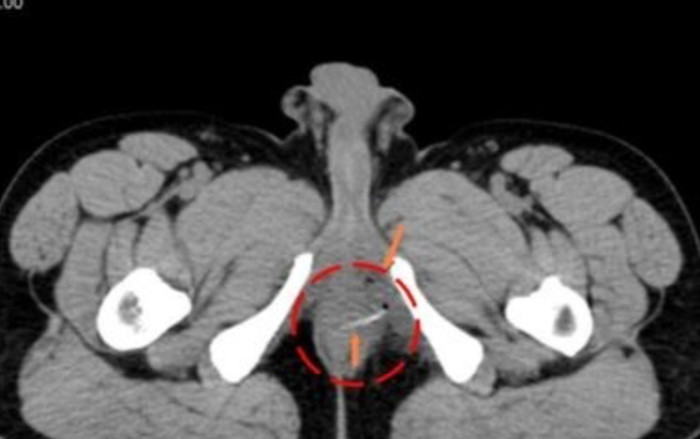

Thông qua kết quả chụp CT Scan toàn thân của bệnh nhân cho thấy một dị vật cản quang hình que kèm bóng khí, gợi ý là xương cá nằm ở vùng trực tràng, đâm thủng thành ruột và tạo áp xe. Sau đó, anh D. đã được nhập bệnh viện Chợ Rẫy phẫu thuật kịp thời lấy dị vật khỏi trực tràng, giảm thiểu tối đa các biến chứng nguy hiểm do dị vật gây ra.